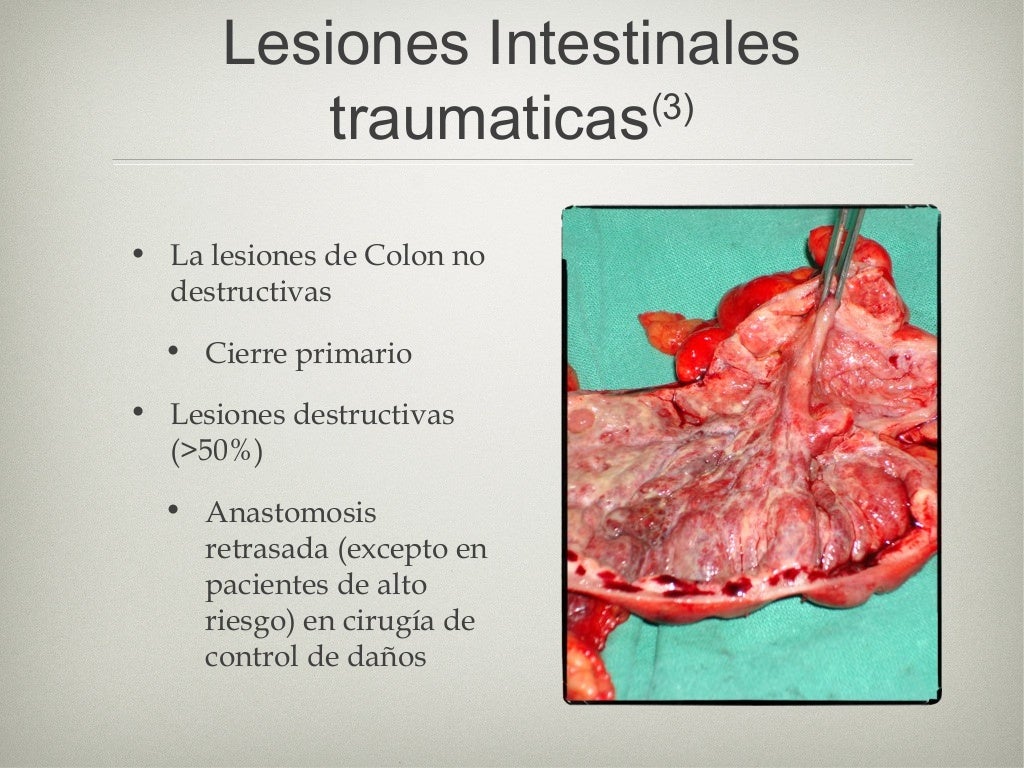

Sepsis intra abdominal

Sepsis intra abdominal

Sepsis intra abdominal

Sepsis intra abdominal